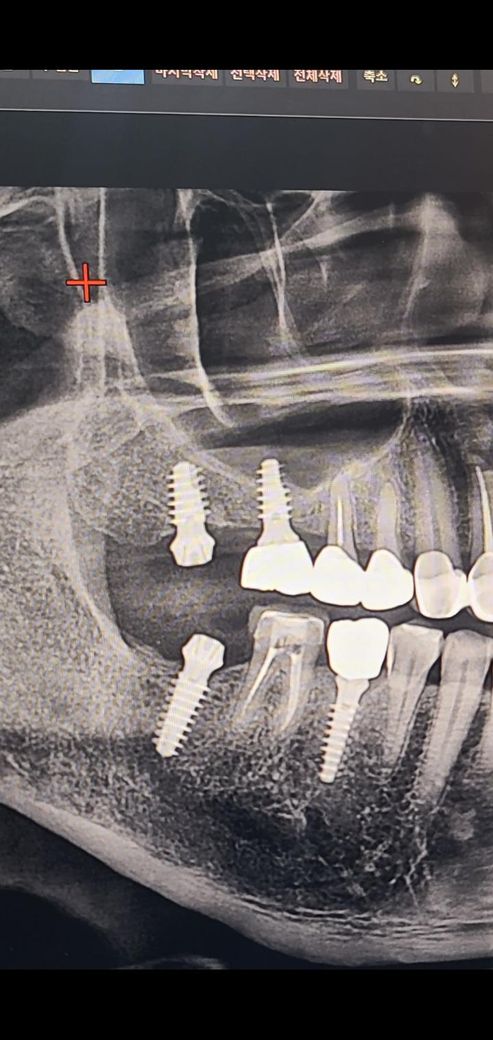

임플란트 상악동 문제는 없는건지요?

17번 오른쪽 위에 맨 끝부분에 임플란트가 현재 보철이 올라온 상태 인데 씹을때 통증이 있고 오른쪽 편두통 까지 오네요

16번과 17번은 상악동 거상술로 인하여 뼈이식을 같이 한다고 하여 1개 값 50만원을 지불 했었고요, ct 상으로 16번, 17번 임플란트 상악동 뼈이식 수술이 잘되었는지 봐주시길 요망합니다. 현재 17번 제거를 심각하게 고려중이 라서요...

엑스레이 상으로는 상악동 거상술 및 뼈이식이 잘된거 같습니다. 보철물이 올라간지 얼마 안됫다면 오랜기간동안 치아를 사용하지 않아서 적응하는데 불편감이 잇을수 있습니다.

임플란트 상악동 문제는 없는건지요? -> 첨부된 엑스레이 사진상 큰 문제는 없어 보입니다, 상악동 뼈이식은 ct 단면상 16번쪽을 봐야 알 수 있습니다